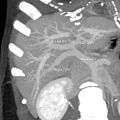

-

MDCT image. Portal venous anatomy contraindicated for liver donation